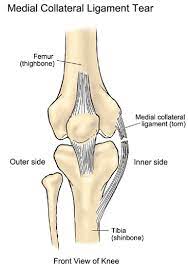

Grade 2 Medial Collateral Ligament Sprain - Medial Collateral Ligament Tear / Knee sprains and meniscal injuries.. Treatment is usually bracing unless there is gross varus instability in which case repair or reconstruction is performed. 3 ways to use video flashcards to engage students and support learning The medial collateral ligament is one of four ligaments that help stabilize the knee.; Our friendly customer care team is here to help you choose the right brace. A medial collateral ligament tear is described by doctors in terms of its severity, and this description can fall into one of three levels.

The medial collateral ligament's main function is to prevent the leg from extending too far inward, but it also helps keep the knee stable and allows it to rotate. Tighten the thigh muscles in your affected leg by pressing the back of your knee flat down to the floor. 3 ways to use video flashcards to engage students and support learning Crutches and restricted weight bearing With a moderate grade ii mcl sprain, the knee ligament tears partially.

It is usually caused by twisting or direct impact, but may develop gradually over time through overuse. A review of ski injuries resulting in combined injury to the anterior cruciate ligament and medial collateral ligaments. Sports medicine and arthroscopy review, 14(2. Knee ligament sprains are graded in severity from one to three: Rehabilitation after injury to the medial collateral ligament of the knee phase 1: Grade iii tears are also usually treated conservatively unless associated with injuries to the anterior cruciate ligament or posterior cruciate ligament. Injuries to the medial collateral ligament most often happen when the knee is hit directly on its outer side. Symptoms of a medial collateral ligament sprain in the elbow will depend if the injury is acute (sudden onset), or if it has developed over time.

Although the knee joint may not hurt or swell very much, a mild ligament sprain can increase a repeat injury risk. Grade i is sprained, grade ii is a partial tear, grade iii is a complete tear of the ligament. There are several classifications for ligament sprains depending on the severity (grade 1, 2 or 3). A grade 3 mcl injury is the most severe type of ligament injury. Sports medicine and arthroscopy review, 14(2. 3 online classroom games to energize your class; The medial collateral ligament's main function is to prevent the leg from extending too far inward, but it also helps keep the knee stable and allows it to rotate. Grade iii tears are also usually treated conservatively unless associated with injuries to the anterior cruciate ligament or posterior cruciate ligament. Conservative and postoperative rehabilitation of isolated and combined injuries of the medial collateral ligament. With a moderate grade ii mcl sprain, the knee ligament tears partially. 3 ways to use video flashcards to engage students and support learning Medial collateral ligament injury of the knee (mcl tear) are the most common ligament injuries of the knee and are frequently associated with acl tears. Symptoms can include moderate pain, swelling, knee instability, and difficulty using the joint.

Chronic injuries will develop gradually over time. Crutches and restricted weight bearing Our friendly customer care team is here to help you choose the right brace. A grade 2 mcl injury means that your ligament has been partially torn. A medial collateral knee ligament sprain or mcl sprain is a tear of the ligament on the inside of the knee. Andrews k, lu a, mckean l, ebraheim n. Injuries to the medial collateral ligament most often happen when the knee is hit directly on its outer side. The medial collateral ligament's main function is to prevent the leg from extending too far inward, but it also helps keep the knee stable and allows it to rotate. The first six weeks after injury (grade 2 and 3) three weeks after injury (grade 1) the knee should be to be protected with a hinged brace for 3 to 6 weeks, depending upon the severity of the injury. Knee sprains and meniscal injuries. Conservative and postoperative rehabilitation of isolated and combined injuries of the medial collateral ligament. 3 online classroom games to energize your class; 3 ways to use video flashcards to engage students and support learning